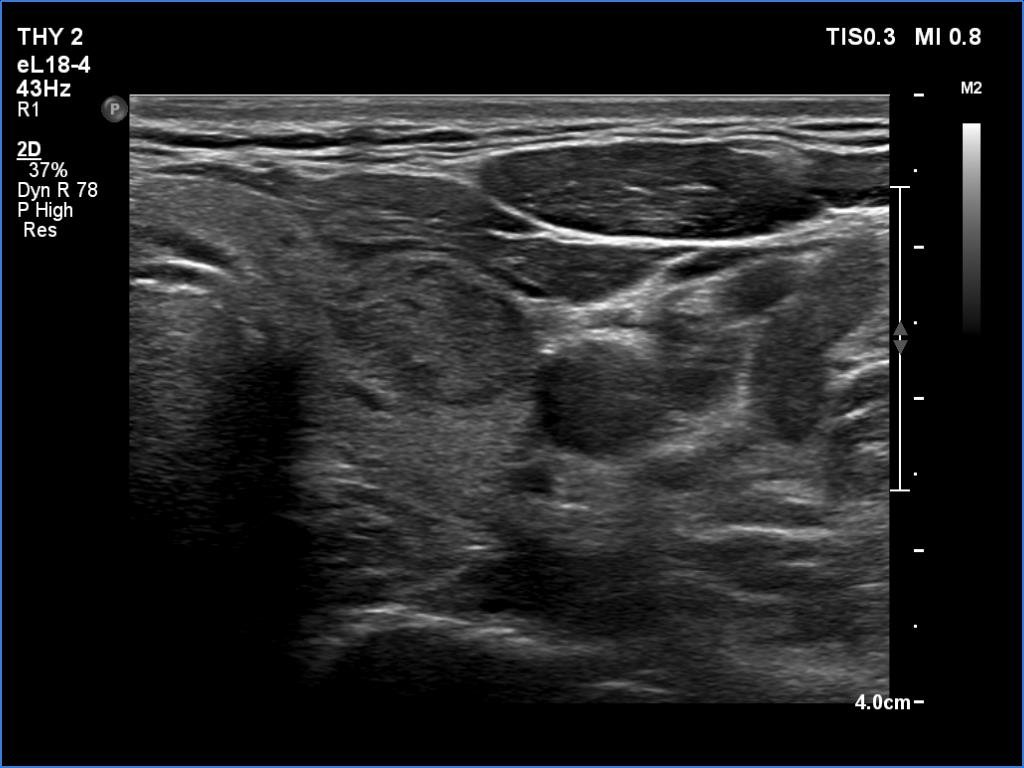

Ultrasonography. The thyroid was echonormal and had multiple minimally/moderately hypoechoic nodules. The lesion in the left lobe was remarkable due to lobulated margins. More than 10 lymph nodes larger than 1 cm in diameter were detected both in the right and the left side of the neck. Some had heterogenous pattern, most of them lacked regular hilum. The vascularity was varied from avascular to obviously irregular.